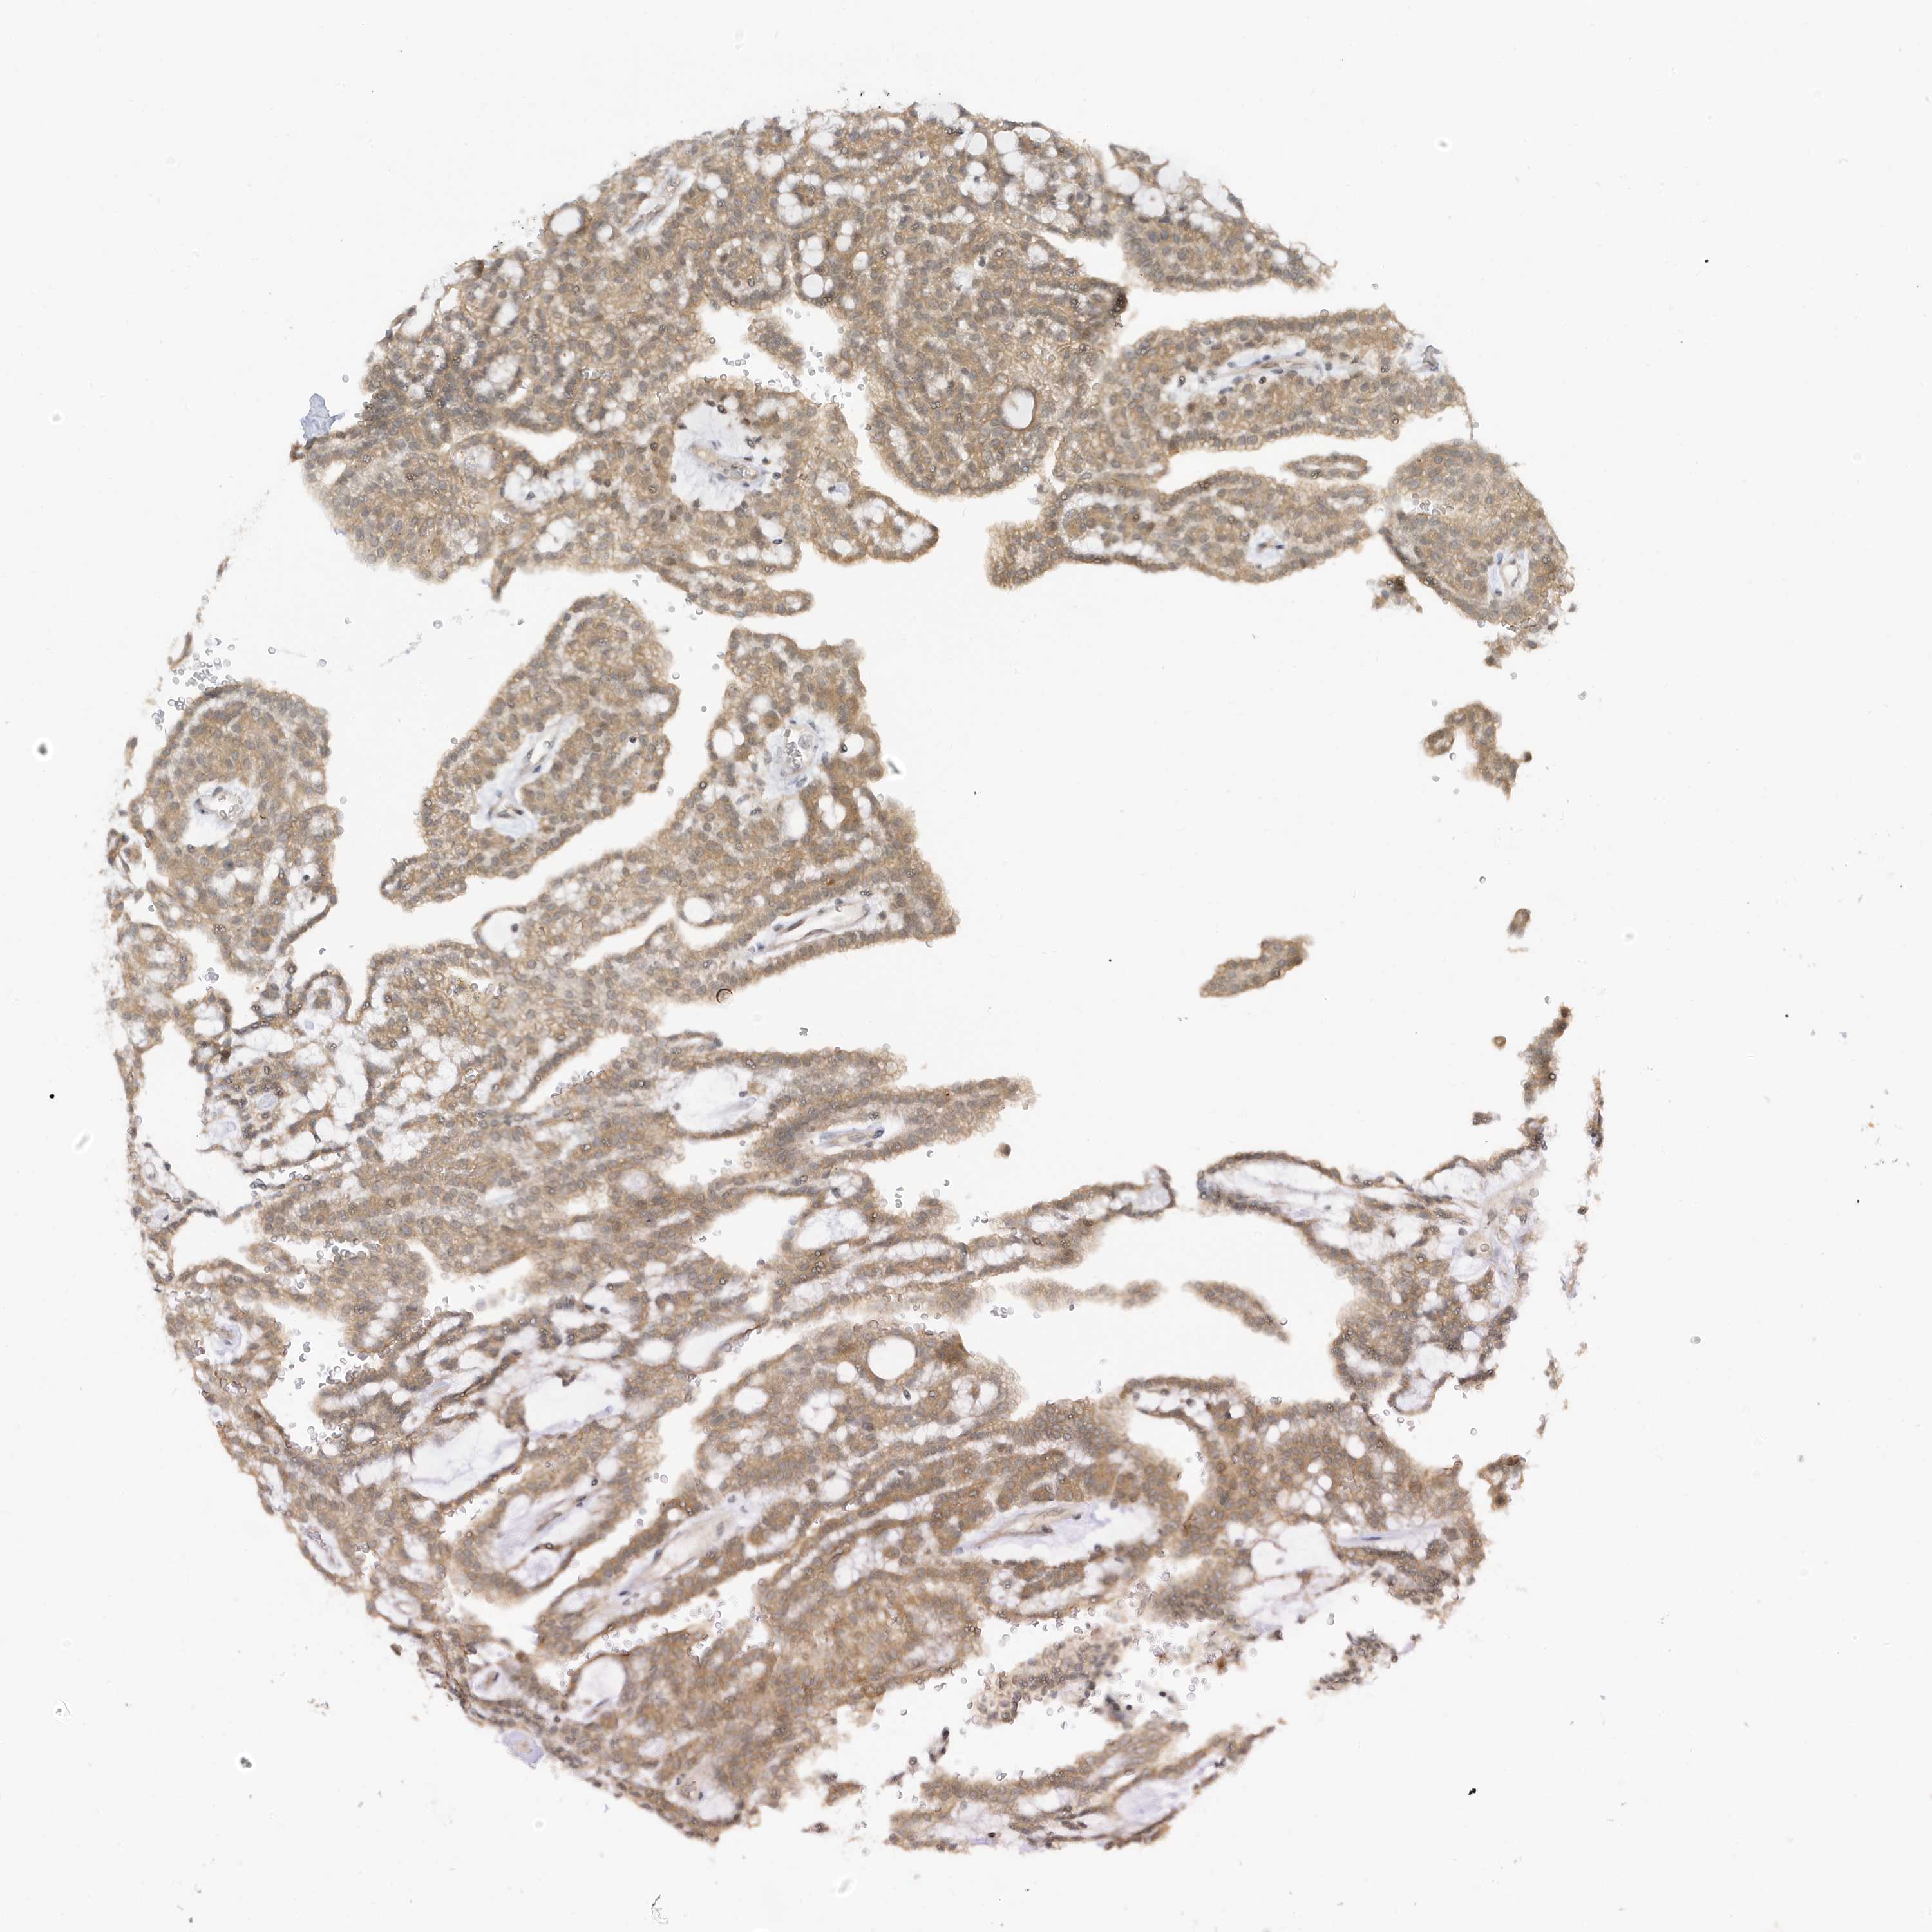

KIDNEY RENAL PAPILLARY CELL CARCINOMA (TCGA) - Interactive survival scatter ploti

TAB3 is not prognostic in Kidney Renal Papillary Cell Carcinoma (TCGA)

Best expression cut offi

Based on the FPKM value of each gene, patients were classified into two groups and association between prognosis (survival) and gene expression (FPKM) was examined. The best expression cut-off refers the FPKM value that yields maximal difference with regard to survival between the two groups at the lowest log-rank P-value. Best expression cut-off was selected based on survival analysis .